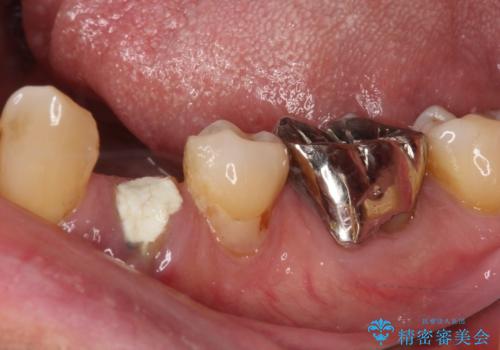

近年の入れ歯は、クラスプという金属のバネのない、ノンクラスプデンチャーが主流となってきており、金属がほとんど使用されなくなっています。しかし、両隣の歯にぶら下がる部分には金属によるフック(レスト)を用いることが、咬み合わせや周辺の歯の安定に大きく寄与するため、今回もレストのみに金属を使用したノンクラスプデンチャーを製作しました。